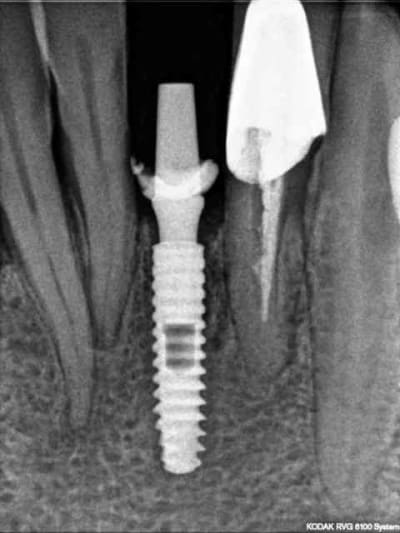

photo 1: début du cas

photo 2: fin d'intervention

photo 3: j+3mois

rx à j=0 et j+4 mois

ce qui est surprenant , c'est la présence d'os au niveau du col.

> rx à j=0 et j+4 mois

>

Oui on connait chez Leone mais reproductible sur toute la gamme. C'est qu"est que je dit! Mais nous c'est démontable et indexé. Un vieux cas en rx 5 ans entre les deux rx.